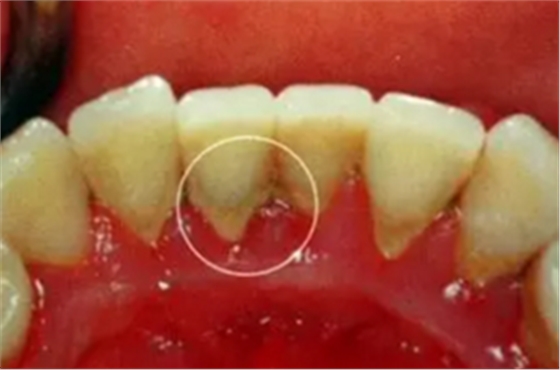

早期癥狀不明顯,患者通常只有繼發(fā)性的牙齦出血或口臭表現(xiàn),與齦炎癥狀相似。檢查可見齦緣、齦乳頭和附著齦的腫脹、質(zhì)松軟,呈深紅色或暗紅色,探診易出血。隨著炎癥的進一步擴散,出現(xiàn)下列癥狀:

牙周袋形成

由于炎癥的擴展,牙周膜被破壞,牙槽骨逐漸吸收,牙齦與牙根分離,使齦溝加深而形成牙周袋。可用探針測牙周袋深度。